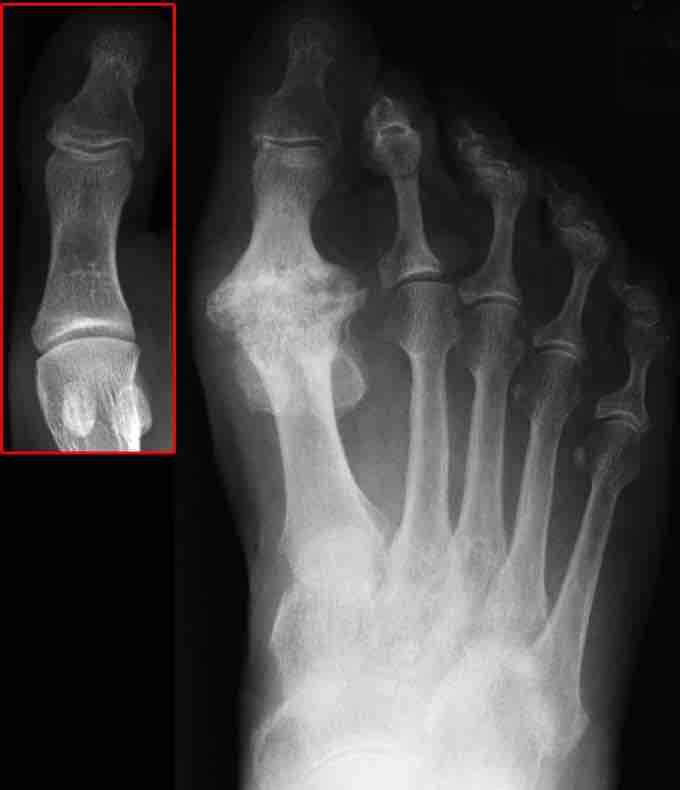

Osteoarthritis

X-ray image of osteoarthritis of the big toe. The red box shows the normal joint.

Osteoarthritis is the degenerative inflammation of the joints, and is the leading cause of disability in people over the age of 55. Osteoarthritis is typically caused by mechanical stress on the joints, resulting in chronic inflammation leading to the loss of cartilage . Osteoarthritis affects the protective cartilage of the joint, causing it to wear down over time, exposing the bone underneath. The bones of the joint then rub together during movement, causing pain and stiffness. As a result of decreased movement secondary to pain, regional muscles may atrophy, and ligaments may become more lax. Osteoarthritis becomes more common as people age, due to increased mechanical stress on the joints.